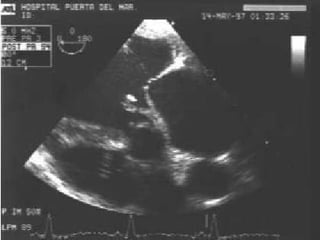

Evidencia de daño miocárdico:   A. ECO positivo para Endocarditis:   (1) Masa intracardiaca móvil,    (2) Abscesos    (3) Prótesis disfuncionante  B.  Insuficiencia valvular nueva

Evidencia de dañomiocárdico: A. ECO positivo para Endocarditis: (1) Masa intracardiaca móvil, (2) Abscesos (3) Prótesis disfuncionante B. Insuficiencia valvular nueva